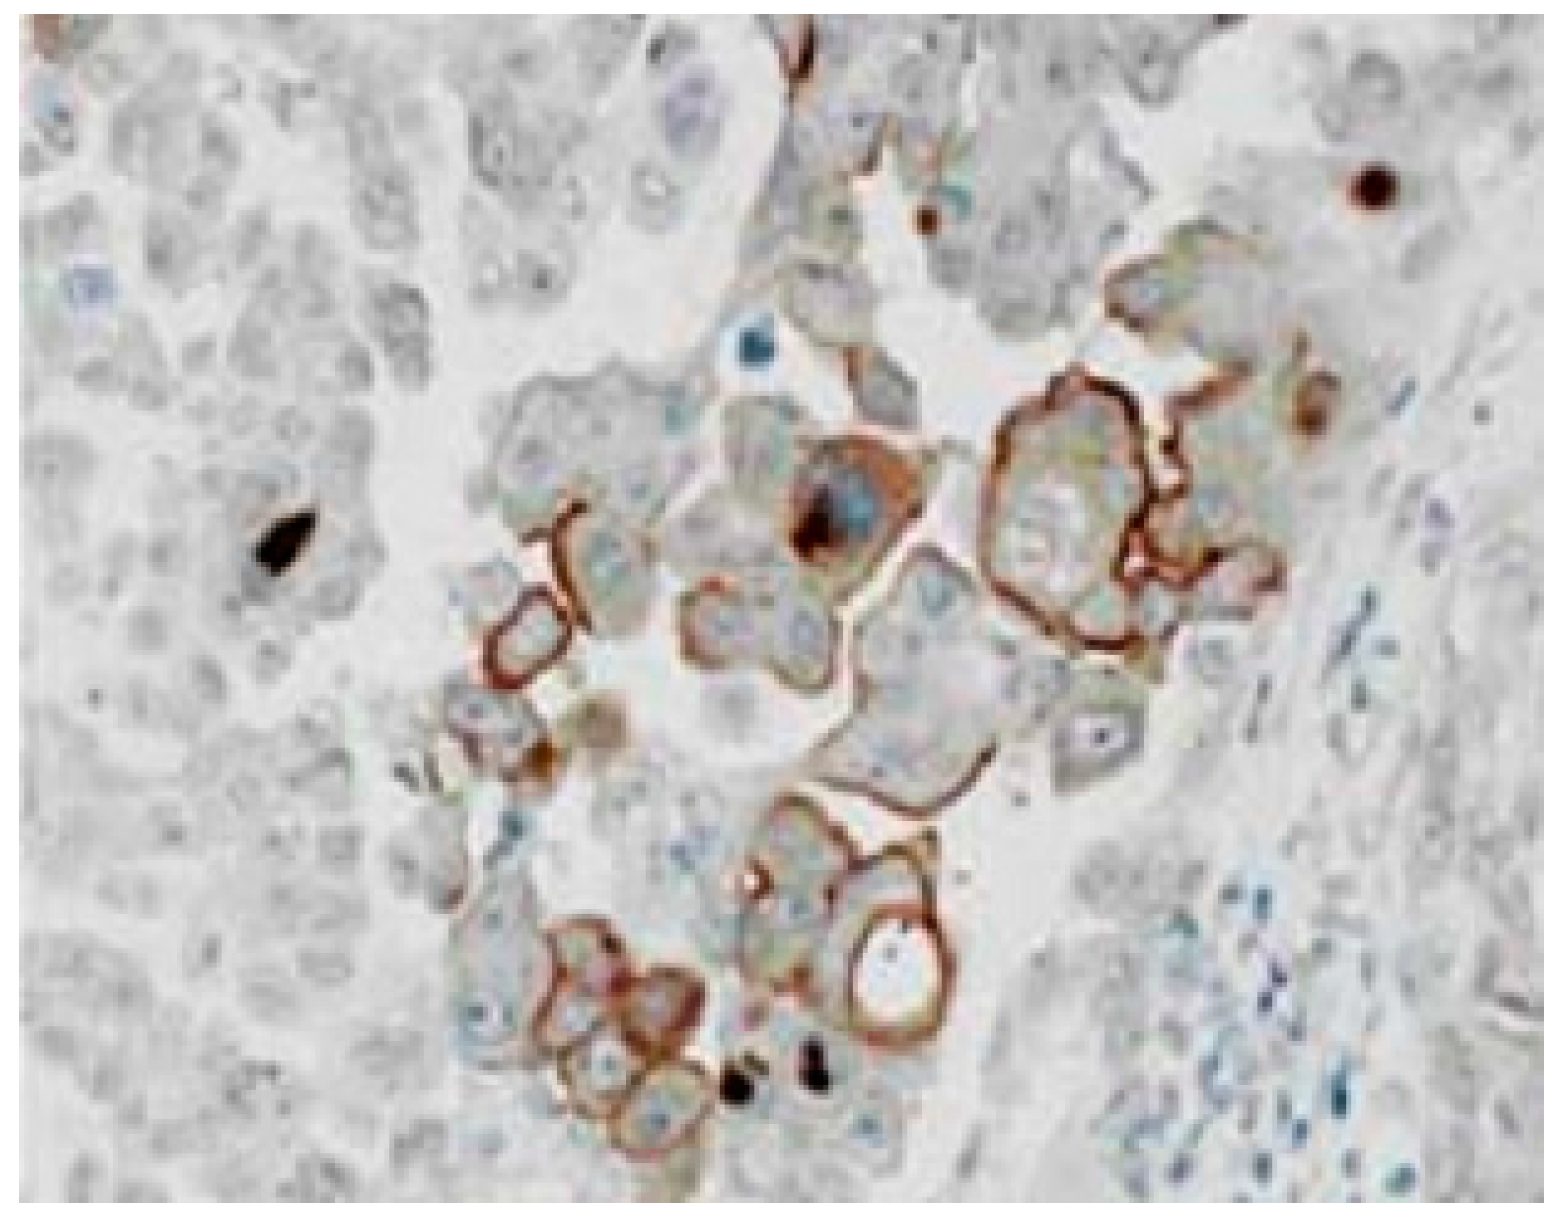

3.1. Immuhohistological Expressions of PEPT1 and ABCG2 Protein